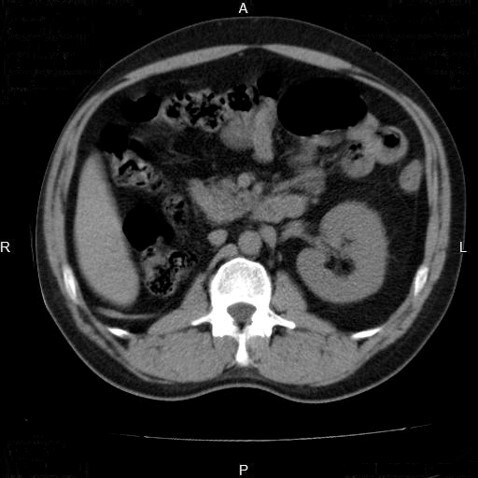

3

Q

What pathology is seen here?

A

Unilateral Renal Agenesis